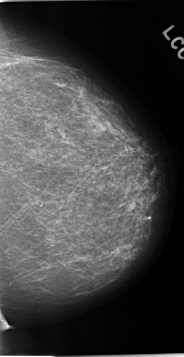

C_0230_1.LEFT_MLO

C_0230_1.LEFT_CC

LEFT_MLO LINES 4688 PIXELS_PER_LINE 2680 BITS_PER_PIXEL 12 RESOLUTION 50 NON_OVERLAY

LEFT_CC LINES 4632 PIXELS_PER_LINE 2392 BITS_PER_PIXEL 12 RESOLUTION 50 NON_OVERLAY